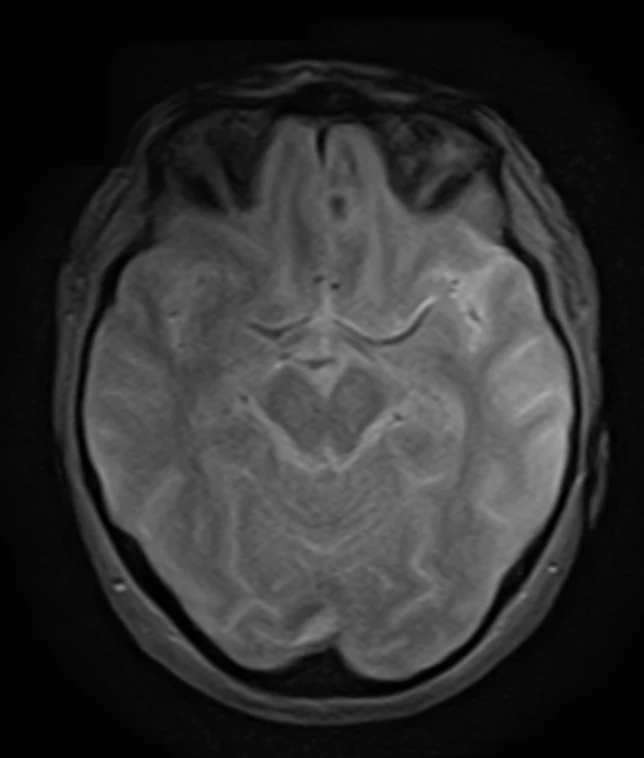

Мужчина 35 лет, месяц назад упал с высоты двух метров, сейчас не полностью ориентирован в месте и времени. Типичная (кроме мозжечка справа) картина травматического аксонального повреждения 3 степени (с поражением ствола). Множественные мелкие точечные и линейные микрокровоизлияния, вокруг части из них видны глиоз/отек. А вот в мозжечке, реально, нечасто такое увидишь. Но бывает. Типа, как вот здесь: